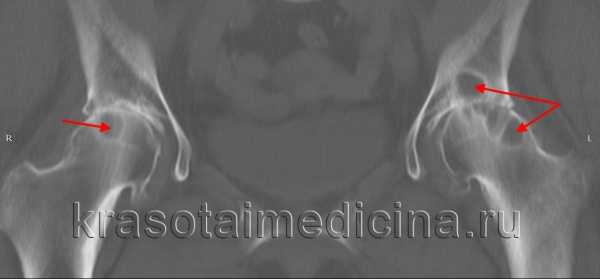

- 2 стадия (импрессионных переломов). На рентгенограмме выявляется гомогенное затемнение, отсутствие структурного рисунка в зоне поражения, локальные уплотнения и снижение высоты головки, расширение суставной щели. Обнаруживается большое количество микропереломов.

- 3 стадия (секвестрации). Головка становится еще более плоской, теряет нормальные контуры, суставная щель продолжает расширяться. На снимках визуализируются отдельные фрагменты кости различного размера и формы, не имеющие нормальной структуры. Определяется утолщение и укорочение шейки бедра.

- 4 стадия (репарации). Фрагментированность костного вещества исчезает. Головка бедренной кости нормально контурируется, однако ее структура еще не восстановлена. В костном веществе иногда просматриваются кистовидные очаги просветления.

- Рентгенография тазобедренного сустава. Для повышения информативности используются специальные укладки по Лаунштейну. Вначале на снимках просматриваются участки со сниженной плотностью под субхондральной костью, придающие поверхностным частям головки вид «яичной скорлупы». Затем становится видна деформация головки и некротический очаг в виде плотной тени, окруженной более светлым ободком. В исходе визуализируются изменения, характерные для деформирующего артроза.